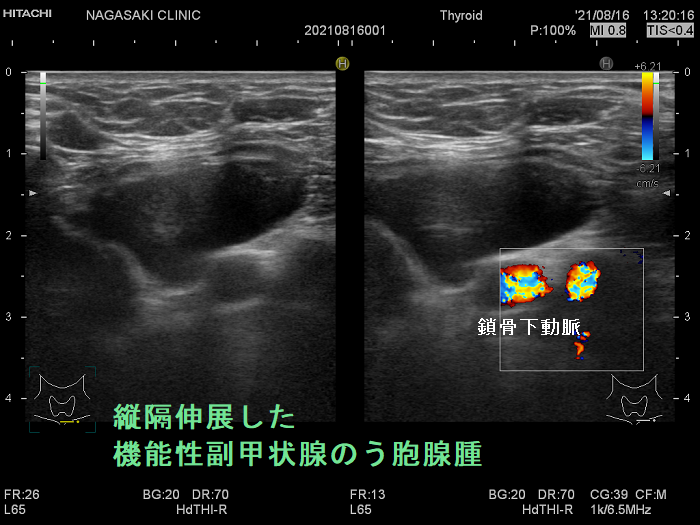

超音波(エコー)検査で見つからない副甲状腺は、

- 縦隔内

- 食道背側

- 喉頭背側

に存在する場合です。

造影CTで副甲状腺腫瘍の位置を再確認します。

原発性副甲状腺機能亢進症手術症例の2.6-6.8%は、定位置にない異所性副甲状腺腫です。縦隔などエコーが届かない場所にある異所性副甲状腺腫に、造影CT, 99m-Tc MIBI-SPECTは有用です。